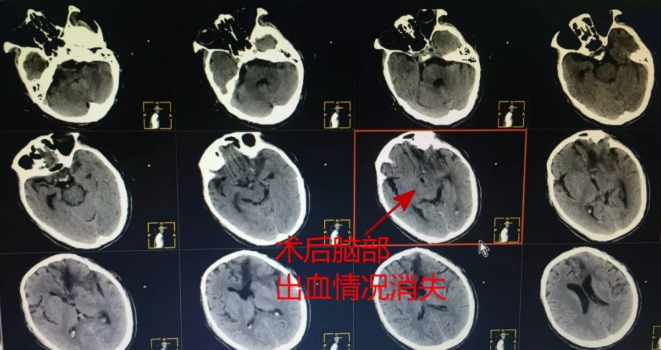

术前CT,王先生脑内大量出血,血肿严重

术后CT,王先生脑部出血情况消失